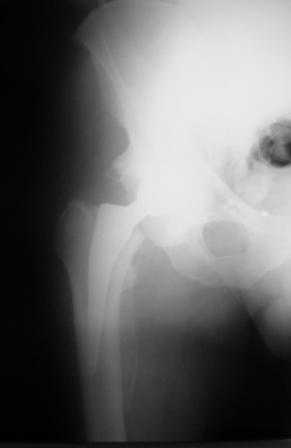

Больной Т. 56 лет, Диагноз: двухсторонний коксартроз 3-4 ст справа, 1-2 ст слева 2.10.08 выполнена операция тотальное бесцементное эндопротезирование. Использовался наружный доступ, положение на боку. Операция протекала без особенностей.

Выполнен послеоперационный ренгеноконтроль в прямой проекции. Рана зажила.

Уважаемый Глеб, предложенные снимки впечатлили! Никто не застрахован...

Больное выписан. Рекомендована ходьба без нагрузки 6 нед, рентгеноконтроль через 2 мес. Явка на консультацию На консультации через 7 недель- Больной ходит с дозированной нагрузкой, умеренные боли по задней поверхности правого бедра. Планируется ревизия. Удаление ножки. Установка такой же ножки Corail.

Приходилось ли кому встречаться с такой ситуацией?Вопросы: вросла ли ножка? Какие могут возникнуть сложности с удалением ножки? Нужна ли будет дополнительная трепанация диафиза? И как? Правильный выбор ножка Corail для ревизии в такой ситуации?